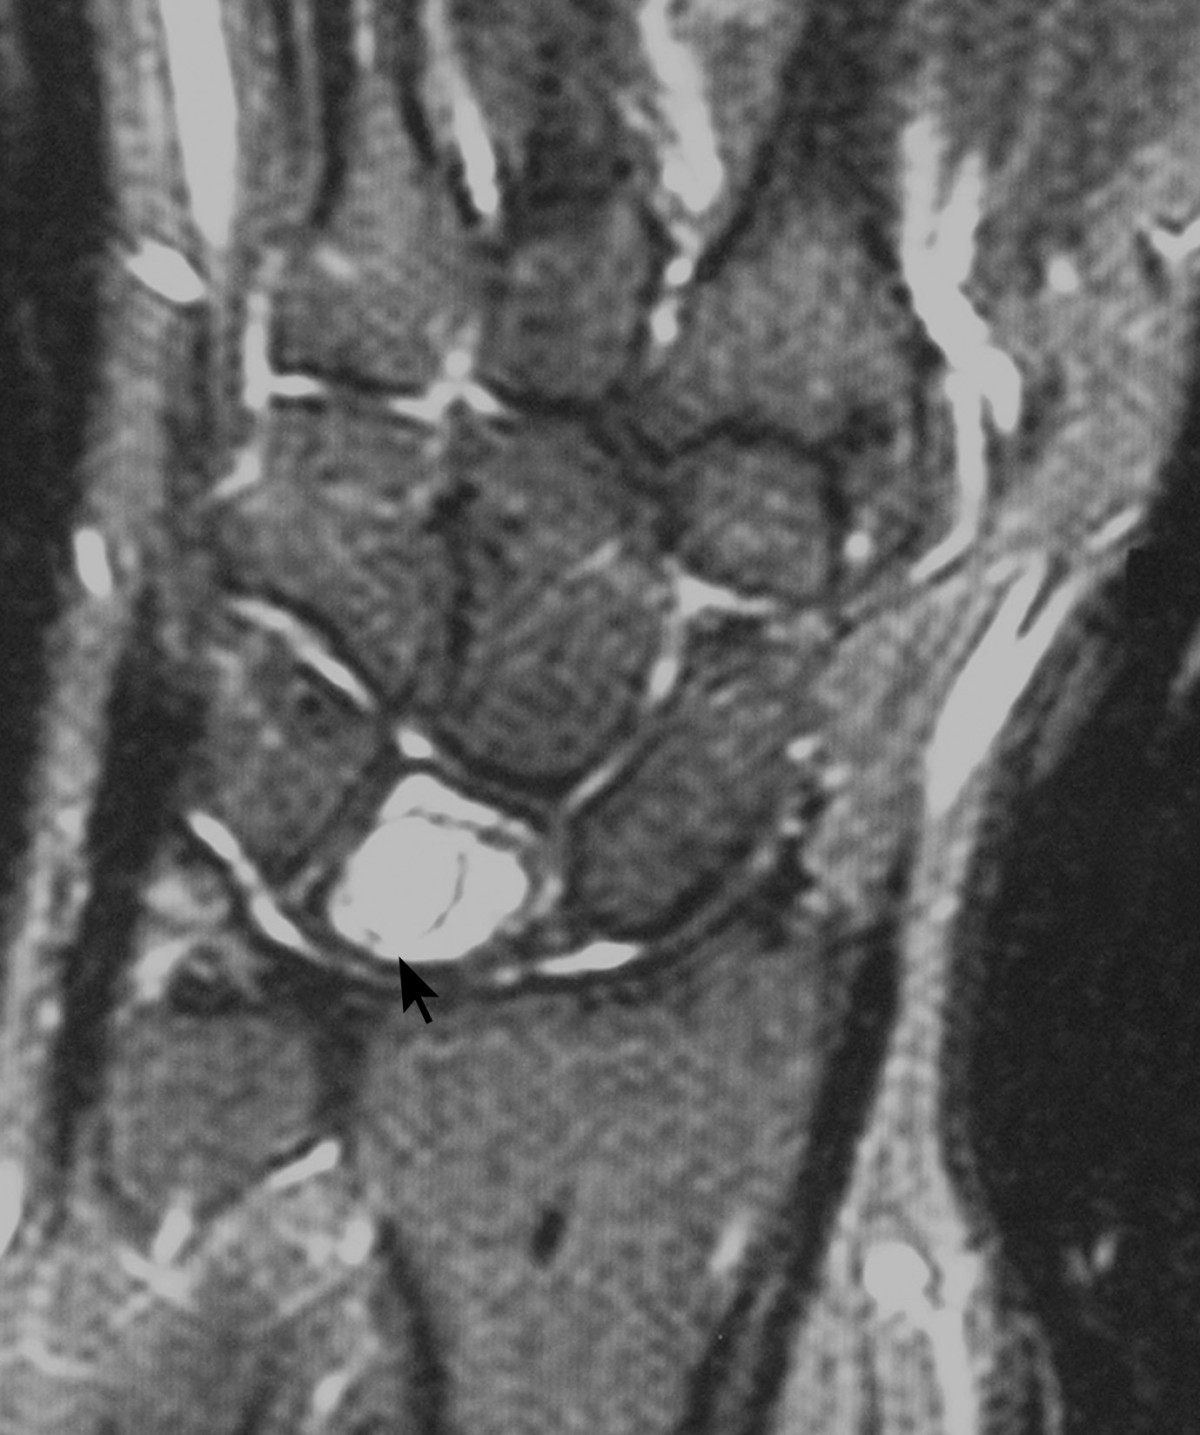

Lunate cyst Radiopaedia What Is A Lunate Cyst This article will answer three questions that the radiologist is often asked: lunate cysts were defined as cystic lesions in the ulnar corner of the lunate as observed on mri or mdct. Where precisely are the cyst and its origin located? this article describes an arthroscopic technique used for lunate intraosseous cyst resection associated. Pain or neurologic symptoms. What Is A Lunate Cyst.

A cyst in lunate and fluid around scaphoid Radiopaedia What Is A Lunate Cyst It is often referred to as lunatomalacia. kienböck disease is the eponymous name given to osteonecrosis involving the lunate. The lunate is one of the eight small bones in the wrist. lunate cysts were defined as cystic lesions in the ulnar corner of the lunate as observed on mri or mdct. This article will answer three questions that. What Is A Lunate Cyst.

A cyst in lunate and fluid around scaphoid Radiopaedia What Is A Lunate Cyst Where precisely are the cyst and its origin located? kienbock’s disease is also known as avascular necrosis (avn) of the lunate. This article will answer three questions that the radiologist is often asked: Are they related to a cyst? lunate cysts were defined as cystic lesions in the ulnar corner of the lunate as observed on mri or. What Is A Lunate Cyst.

A cyst in lunate and fluid around scaphoid Radiopaedia What Is A Lunate Cyst Where precisely are the cyst and its origin located? lunate cysts were defined as cystic lesions in the ulnar corner of the lunate as observed on mri or mdct. Pain or neurologic symptoms are present; Are they related to a cyst? ganglion cysts are common hand masses. this article describes an arthroscopic technique used for lunate intraosseous. What Is A Lunate Cyst.